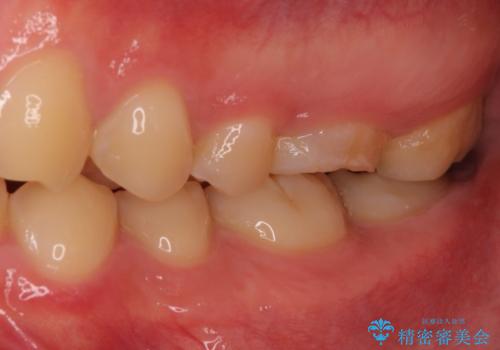

根管治療中の転院 奥歯のオールセラミック治療

根管治療を実施した後、フルジルコニアクラウンに補綴することとしました。

前医での処置後、治療前には気にならなかった痛み続いていたようですが、当院での処置後は痛みが徐々に引いていき、治療から半年が経過した時点では全く違和感も感じなくなりました。

根管治療後のクラウンも、まるでもとの自分の歯のように自然な仕上がりとなり、患者様には大変満足していただけました。